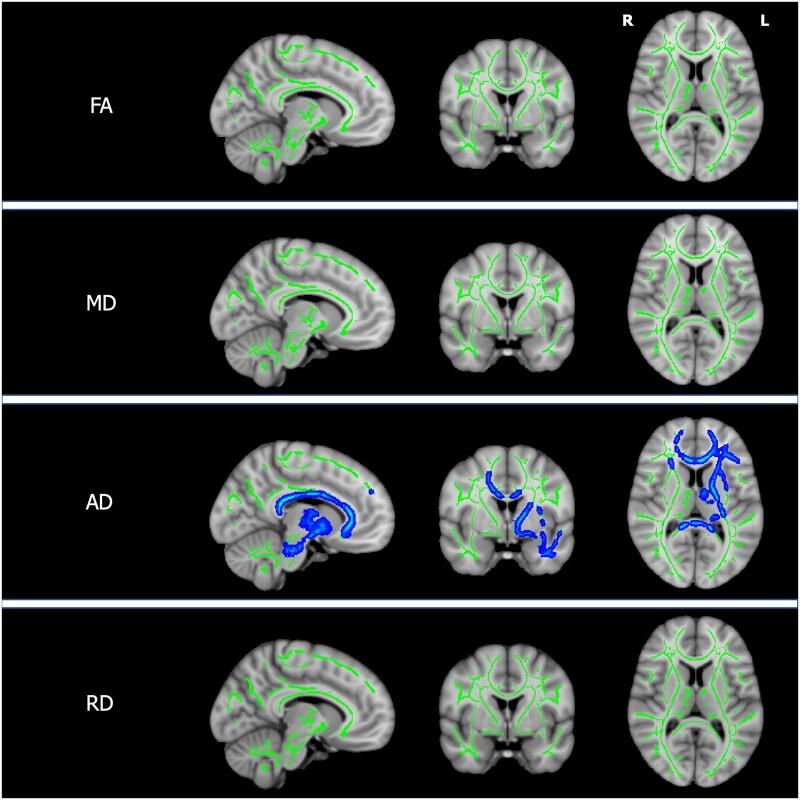

Wilson's disease is an autosomal-recessive disorder of copper metabolism with neurological and hepatic presentations. Chelation therapy is used to 'de-copper' patients but neurological outcomes remain unpredictable. A range of neuroimaging abnormalities have been described and may provide insights into disease mechanisms, in addition to prognostic and monitoring biomarkers. Previous quantitative MRI analyses have focused on specific sequences or regions of interest, often stratifying chronically treated patients according to persisting symptoms as opposed to initial presentation. In this cross-sectional study, we performed a combination of unbiased, whole-brain analyses on T1-weighted, fluid-attenuated inversion recovery, diffusion-weighted and susceptibility-weighted imaging data from 40 prospectively recruited patients with Wilson's disease (age range 16-68). We compared patients with neurological (n = 23) and hepatic (n = 17) presentations to determine the neuroradiological sequelae of the initial brain injury. We also subcategorized patients according to recent neurological status, classifying those with neurological presentations or deterioration in the preceding 6 months as having 'active' disease. This allowed us to compare patients with active (n = 5) and stable (n = 35) disease and identify imaging correlates for persistent neurological deficits and copper indices in chronically treated, stable patients. Using a combination of voxel-based morphometry and region-of-interest volumetric analyses, we demonstrate that grey matter volumes are lower in the basal ganglia, thalamus, brainstem, cerebellum, anterior insula and orbitofrontal cortex when comparing patients with neurological and hepatic presentations. In chronically treated, stable patients, the severity of neurological deficits correlated with grey matter volumes in similar, predominantly subcortical regions. In contrast, the severity of neurological deficits did not correlate with the volume of white matter hyperintensities, calculated using an automated lesion segmentation algorithm. Using tract-based spatial statistics, increasing neurological severity in chronically treated patients was associated with decreasing axial diffusivity in white matter tracts whereas increasing serum non-caeruloplasmin-bound ('free') copper and active disease were associated with distinct patterns of increasing mean, axial and radial diffusivity. Whole-brain quantitative susceptibility mapping identified increased iron deposition in the putamen, cingulate and medial frontal cortices of patients with neurological presentations relative to those with hepatic presentations and neurological severity was associated with iron deposition in widespread cortical regions in chronically treated patients. Our data indicate that composite measures of subcortical atrophy provide useful prognostic biomarkers, whereas abnormal mean, axial and radial diffusivity are promising monitoring biomarkers. Finally, deposition of brain iron in response to copper accumulation may directly contribute to neurodegeneration in Wilson's disease.